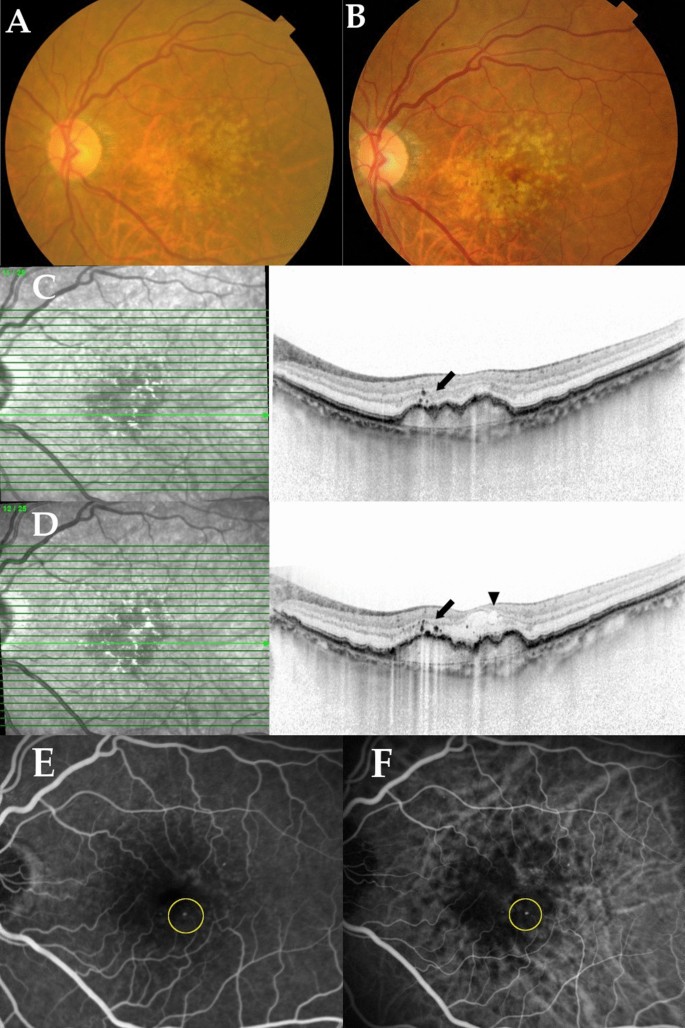

A total of 155 patients with intermediate AMD, who had treatment naïve MNV in the contralateral eye at baseline, were included in this study. Table 1 shows the baseline demographic and genetic characteristics of participants. The mean age was 77.8 ± 7.6 years and 52 patients (33.5%) were women. Of 155 eyes, HRF was observed in 53 eyes (34.2%). The MNV subtypes in the contralateral eye were type 3 MNV (n = 23, 14.8%), typical neovascular AMD (n = 82, 52.9%), and polypoidal choroidal vasculopathy (PCV, n = 50, 32.3%). Figure 1 shows representative cases of HRF at initial presentation that indicate the development of type 3 MNV during the follow-up period.

A representative case of a 71-year-old woman with intermediate age-related macular degeneration (AMD) colocalizing with hyperreflective foci (HRF) in the left eye and type-3 macular neovascularization (MNV) in right eye. (A) Color fundus photography of the left eye at the initial appearance demonstrates drusenoid pigment epithelial detachment (DPED) surrounded by reticular pseudodrusen in the macular area. (B) At 7 months after initial presentation, color fundus photography of the left eye demonstrates the development of intraretinal hemorrhage in the macular area. (C) A horizontal scan through the fovea by spectral-domain optical coherence tomography (SD-OCT) in the left eye at the initial appearance shows HRF (black arrow) near the protrusion of DPED. (D) A horizontal SD-OCT scan through the fovea of the left eye at 7 months shows the presence of intraretinal fluid (black arrowhead) and increased HRF (black arrow). (E) Fluorescein angiography and (F) indocyanine angiography of the left eye at 7 months shows a hot spot (yellow circle) that is consistent with type-3 MNV.